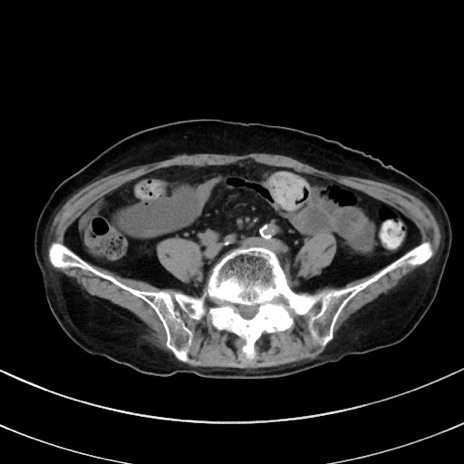

症例33(横断像)

【症例】70歳代 女性

【主訴】心窩部痛

【現病歴】延髄病変の精査・加療にて神経内科入院中。本日より心窩部痛あり。

【既往歴】虫垂炎

【身体所見】右下腹部を中心に圧痛と反跳痛あり。

【データ】WBC 10900、CRP 0.02